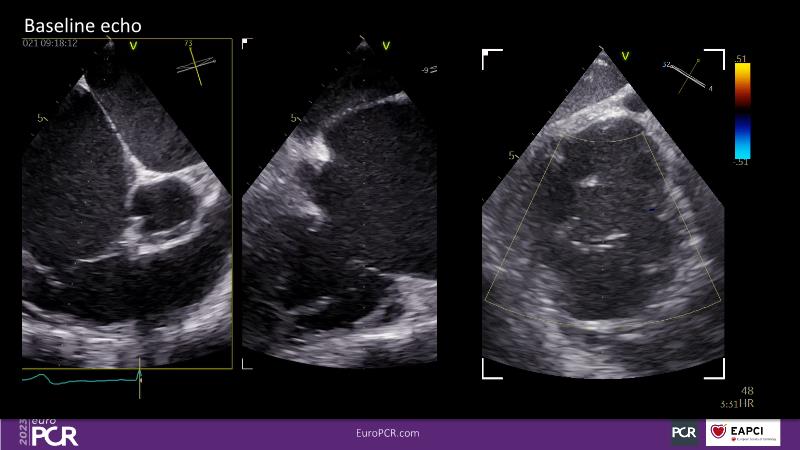

Tailoring tricuspid regurgitation patient treatment with the PASCAL Precision system

- To discuss the different tricuspid regurgitation phenotypes that can be treated with the PASCAL Precision repair system

- To participate in a case-based discussion using the PASCAL Precision repair system for the treatment of tricuspid regurgitation